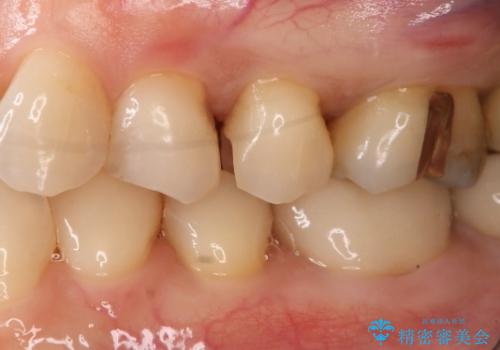

- 左上奥歯の銀歯のやり変えを希望された患者様です。

白くしたいとの事だったので形態・切削量を考慮し、セラミックインレーでの治療を計画しました。

保険材料と比較し、セラミックは劣化しない材料なので二次的な虫歯を防ぐことが出来ます。